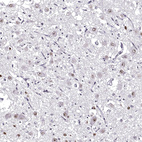

Immunohistochemical staining of human hypothalamus shows nuclear positivity in neurons.